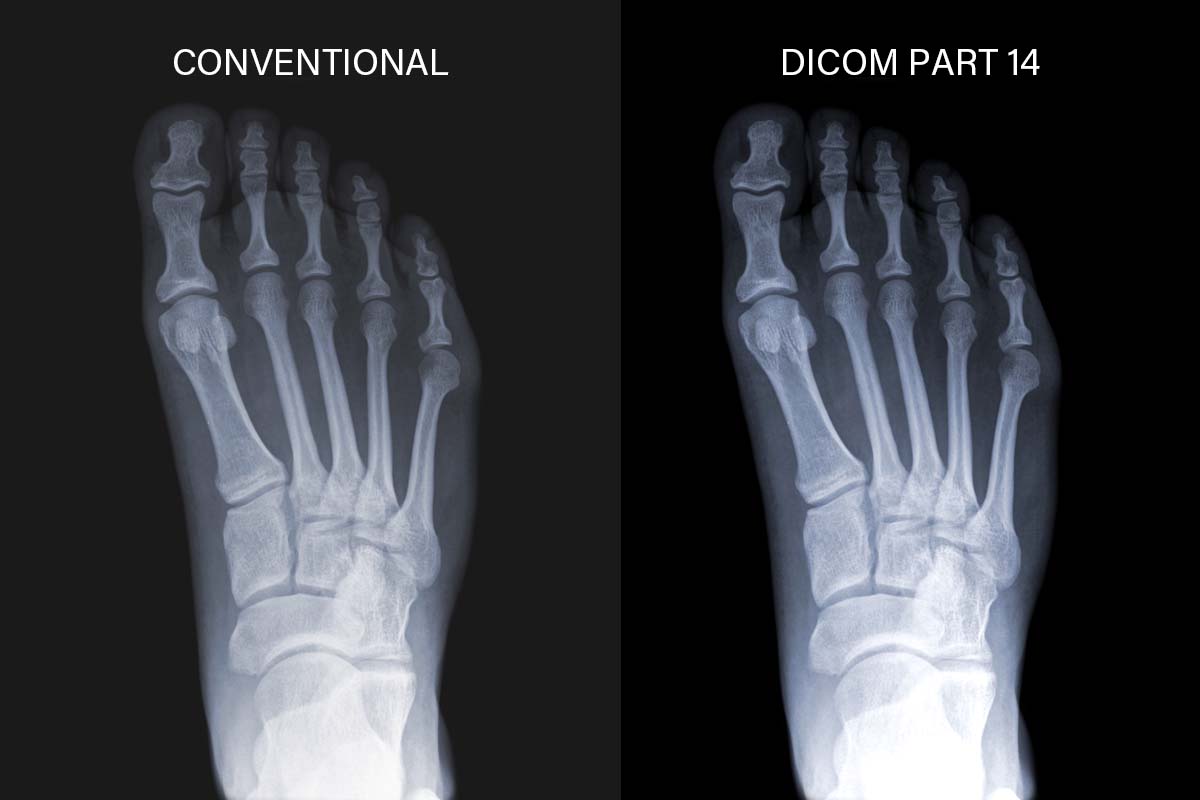

Сумісність із DICOM Part 14

Завдяки підтримці калібрування DICOM Part 14 монітори для клінічного огляду серії MD забезпечують точну та стабільну яскравість, а також рівень відтінків сірого на зображеннях. Це дає медичним фахівцям впевненість у якості переглянутих зображень, документів та електронних медичних записів з підтримкою зображень (EMR).